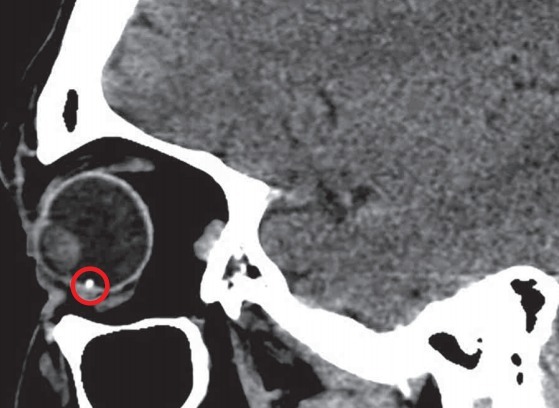

尽管未见眼内异物,根据患者临床表现可推断其为眼球铁质沉着症,进一步通过眼眶 CT,发现球状金属异物(图 2)。

图 2 为借助眼眶 CT,发现球状金属异物